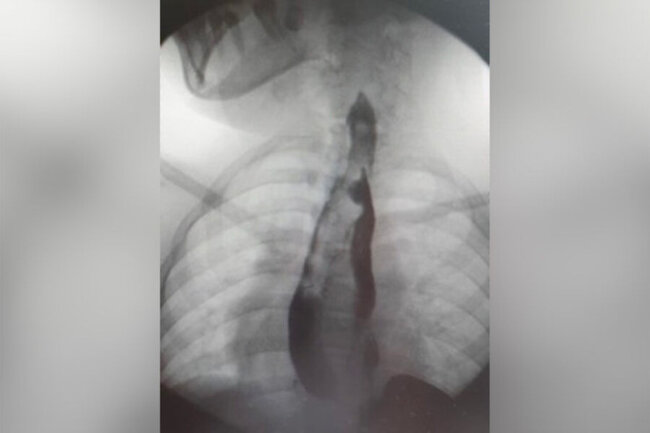

Sonxeber.az bildirir ki, 14 yaşlı məktəbli qız qarın nahiyəsində vaxtaşırı ağrılardan şikayətləndiyi üçün ailə yaşadıqları yer üzrə klinikaya müraciət edib. Müayinə zamanı nadir bir patoloji - yemək borusu və mədənin qoşa olması aşkarlanıb.

Hər iki cüt orqan, demək olar ki, bütün uzunluğu boyunca tam formalaşıb. Qız sonrakı müalicə üçün Moskvadakı Rusiya Uşaq Klinik Xəstəxanasına göndərilib.

"Klinik praktikada ən çox rast gəlinən növ həzm traktının kiçik bir hissəsinin kistik təkrarlanmasıdır. Ən çox da hallarda nazik bağırsağın. Həm özofagusun, həm də mədənin belə genişlənmiş ikiqat artması, hətta xarici təcrübədə də olduqca nadir bir vəziyyətdir. 40 illik təcrübəmizdə heç vaxt belə böyüklükdə patologiyaya rast gəlməmişik", - Rusiya Uşaq Klinik Xəstəxanasının döş qəfəsinin rekonstruktiv və rekonstruktiv cərrahiyyəsi şöbəsinin həkimi Sergey Makarov bildirib.

Həkimlər mürəkkəb əməliyyat keçirərək qoşalaşmış orqanları çıxarıblar. Cərrahi müdaxilə uğurlu olub və reabilitasiya kursundan sonra qız ambulator müalicəyə buraxılıb./Lent.az